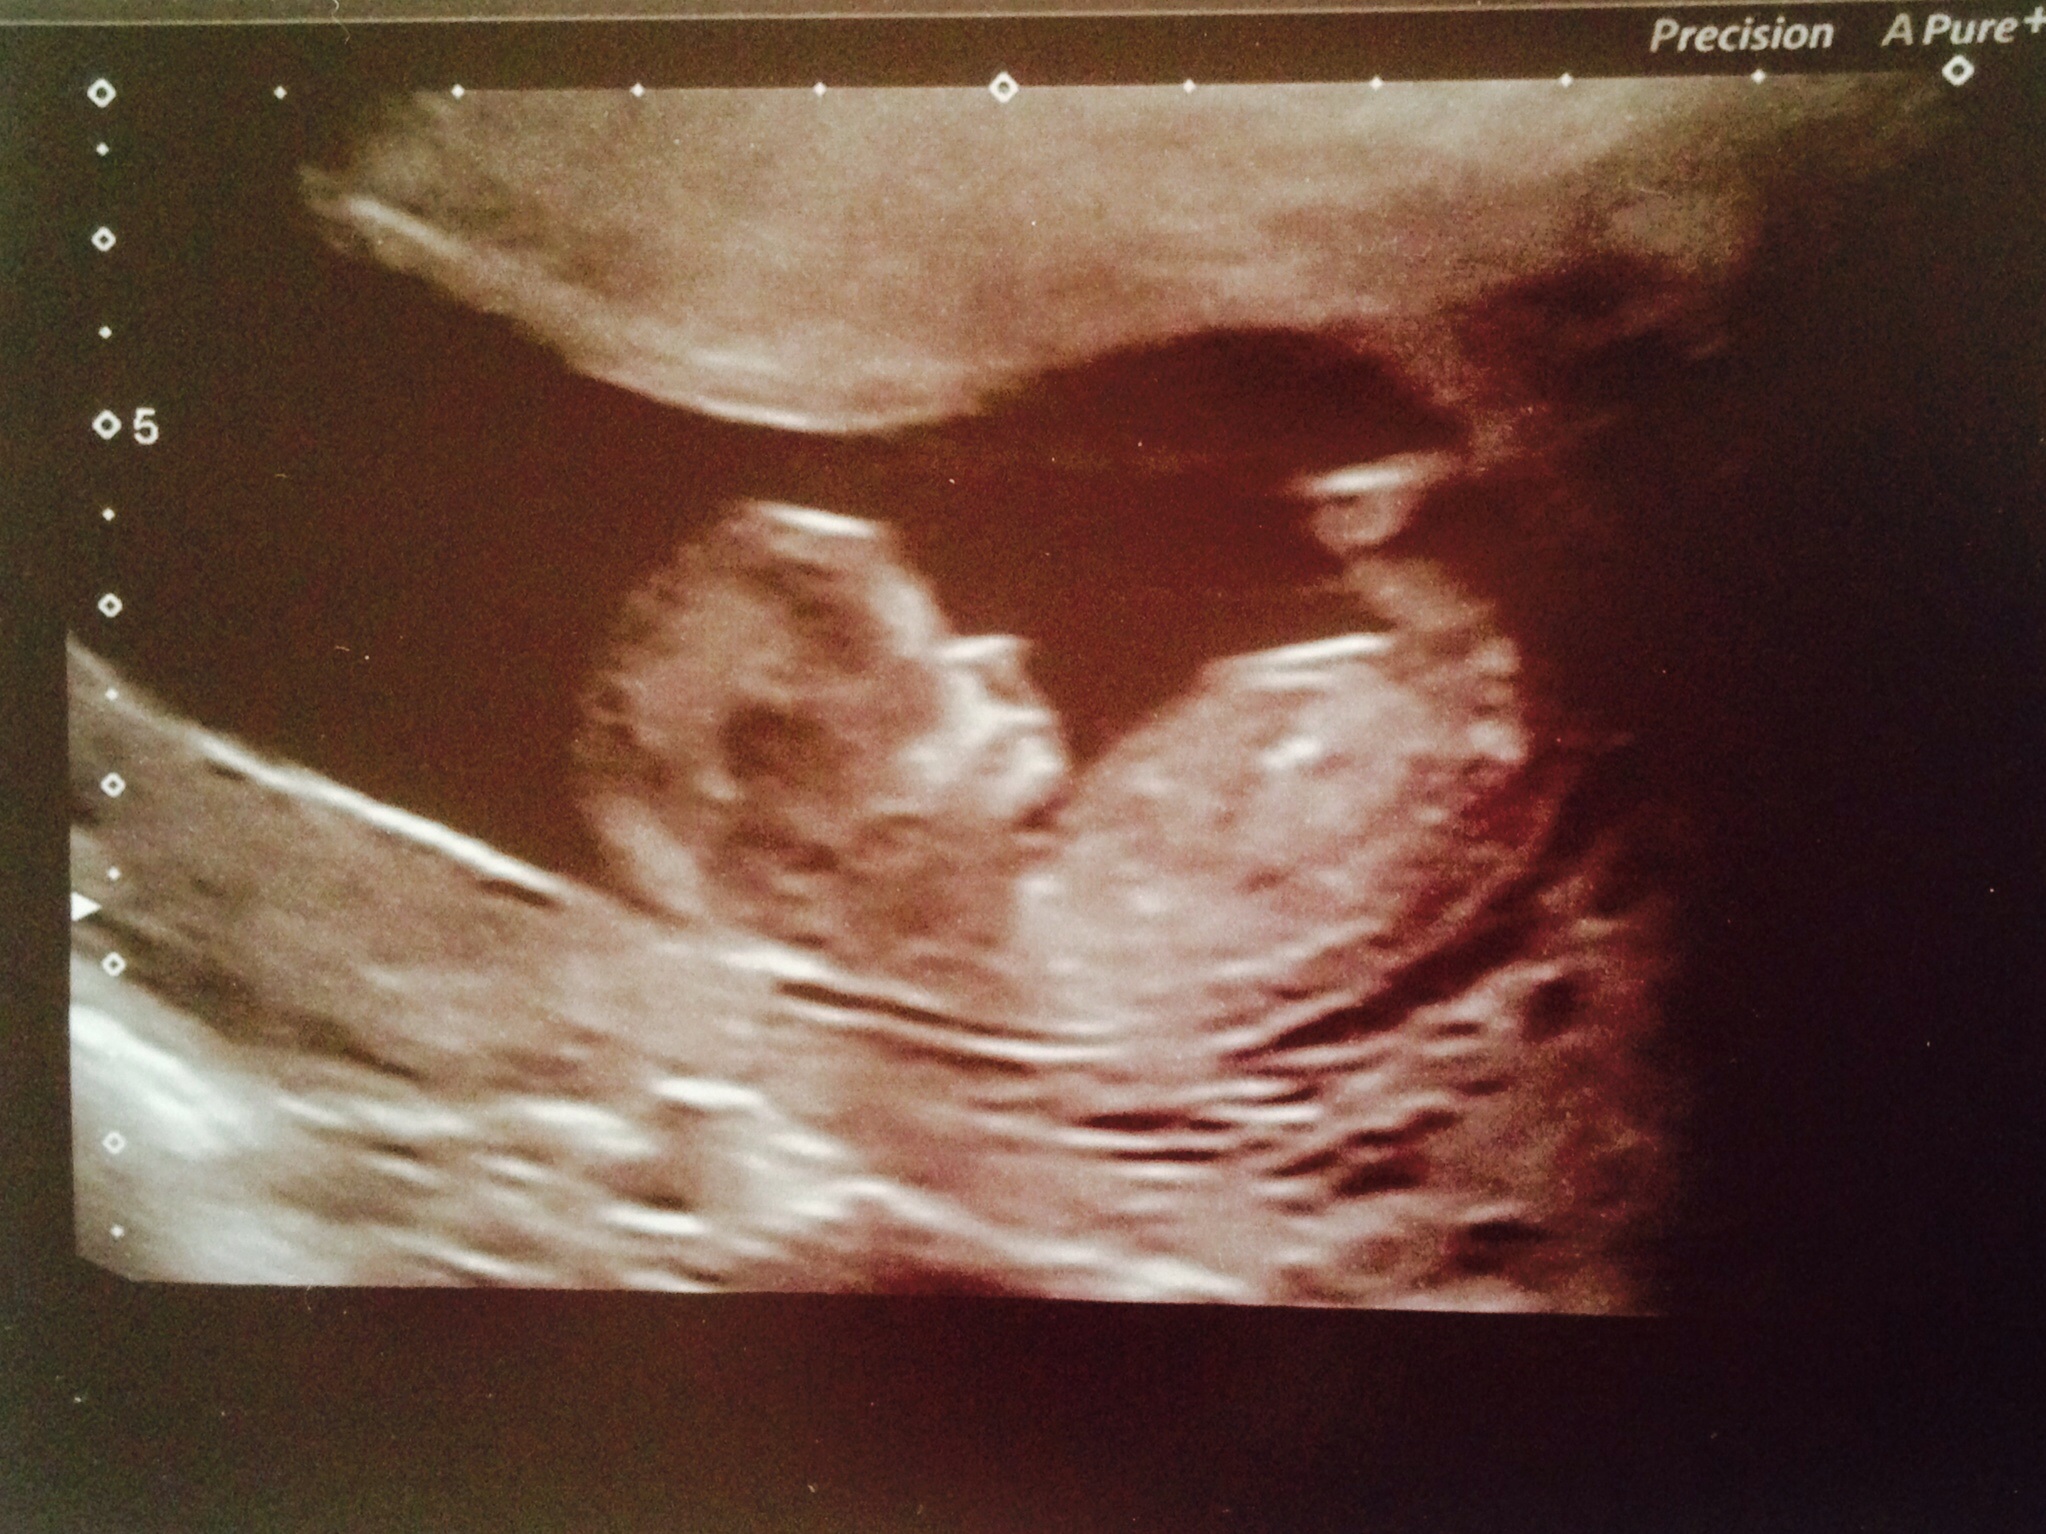

Here are my twins from my 13 week ultrasound. Both have strong heartbeats! One measuring at 13 weeks 4 days and the other 13 weeks 6 days. Tech made a guess and thinks they're boys!!